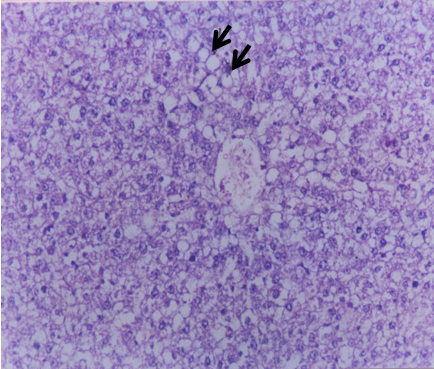

Histopathological results

Our results (Figure 1 [Fig. 1], Figure 2 [Fig. 2], Figure 3 [Fig. 3], Figure 4 [Fig. 4], Figure 5 [Fig. 5], Figure 6 [Fig. 6], Figure 7 [Fig. 7]) revealed that treatment of the PC group with FO or OO supplemented with vitamins E & C led to the best improvement. The histopathological investigation showed apparently normal hepatocytes.

In this respect, Alwayn et al. [24] reported that supplementation of n-3 FAs can ameliorate hepatic steatosis in a murine model of parenteral nutrition as demonstrated by histology. In this concern, Cohen et al. [25] found that n-3 PUFA as found in FO has anti-inflammatory properties that are mediated by the production of anti-inflammatory eicosanoids.

Little data are available on the effect of supplemented diets with vitamin E and C on intoxicated rat livers with CCl4. The histological results confirmed that the hepatically injured rats with CCl4 and fed on supplemented FOEC or OOEC showed apparently normal hepatocytes.